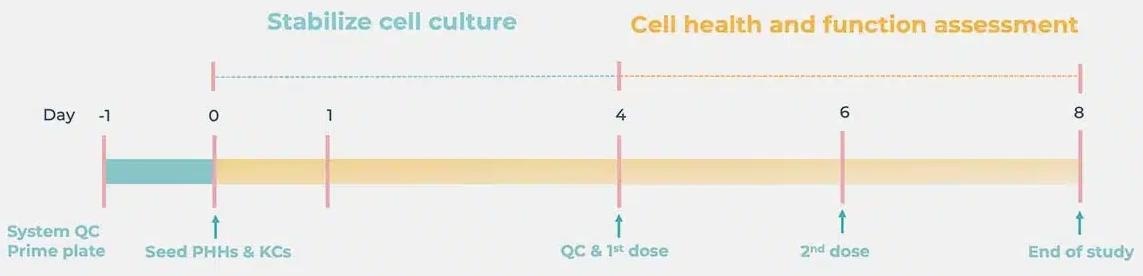

Standard DILI cell culture timeline

Image Credit: CN-Bio